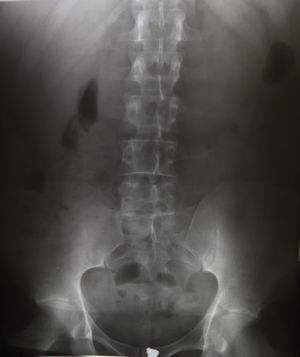

4. 1. 단순 X선 촬영

단순 X선 촬영은 물체를 X선 또는 기타 고에너지 형태의 전자기파에 노출시켜 생성된 잔류 빔(또는 "음영")을 잠상으로 포착하여 이미지를 생성하는 "투사 방사선 촬영"의 일종이다.[32] 뼈와 일부 장기(예: 폐)는 투사 방사선 촬영에 적합하며, 비교적 저렴한 검사로 높은 진단 수율을 보인다.[32] 뢴트겐이 X선을 발견한 이후, 의료 분야에서는 주로 뼈나 폐의 병변을 그려내는 영상 진단으로서 적극적으로 이용되어 왔다.

단순 X선 촬영의 주요 이용법은 다음과 같다.